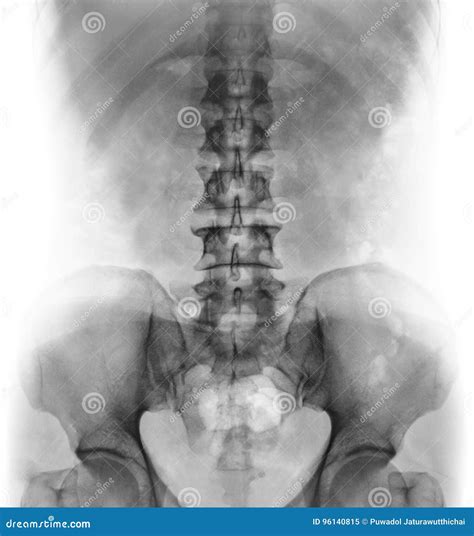

A Lower Back X Ray is a common, non-invasive imaging test that uses a small amount of radiation to create pictures of the lumbar spine. The lumbar spine consists of the five vertebrae in your lower back. By capturing these images, doctors can evaluate the bones, joints, and overall alignment of the lower spine.

Undergoing a Lower Back X Ray is a straightforward and generally quick process. You will be asked to change into a hospital gown to ensure no metal objects, like zippers or jewelry, interfere with the image quality. You may be required to stand, sit, or lie down in different positions—such as on your side or back—so the technician can capture images from multiple angles. This ensures a comprehensive view of the lumbar region.

What Can Be Seen on a Lower Back X Ray?